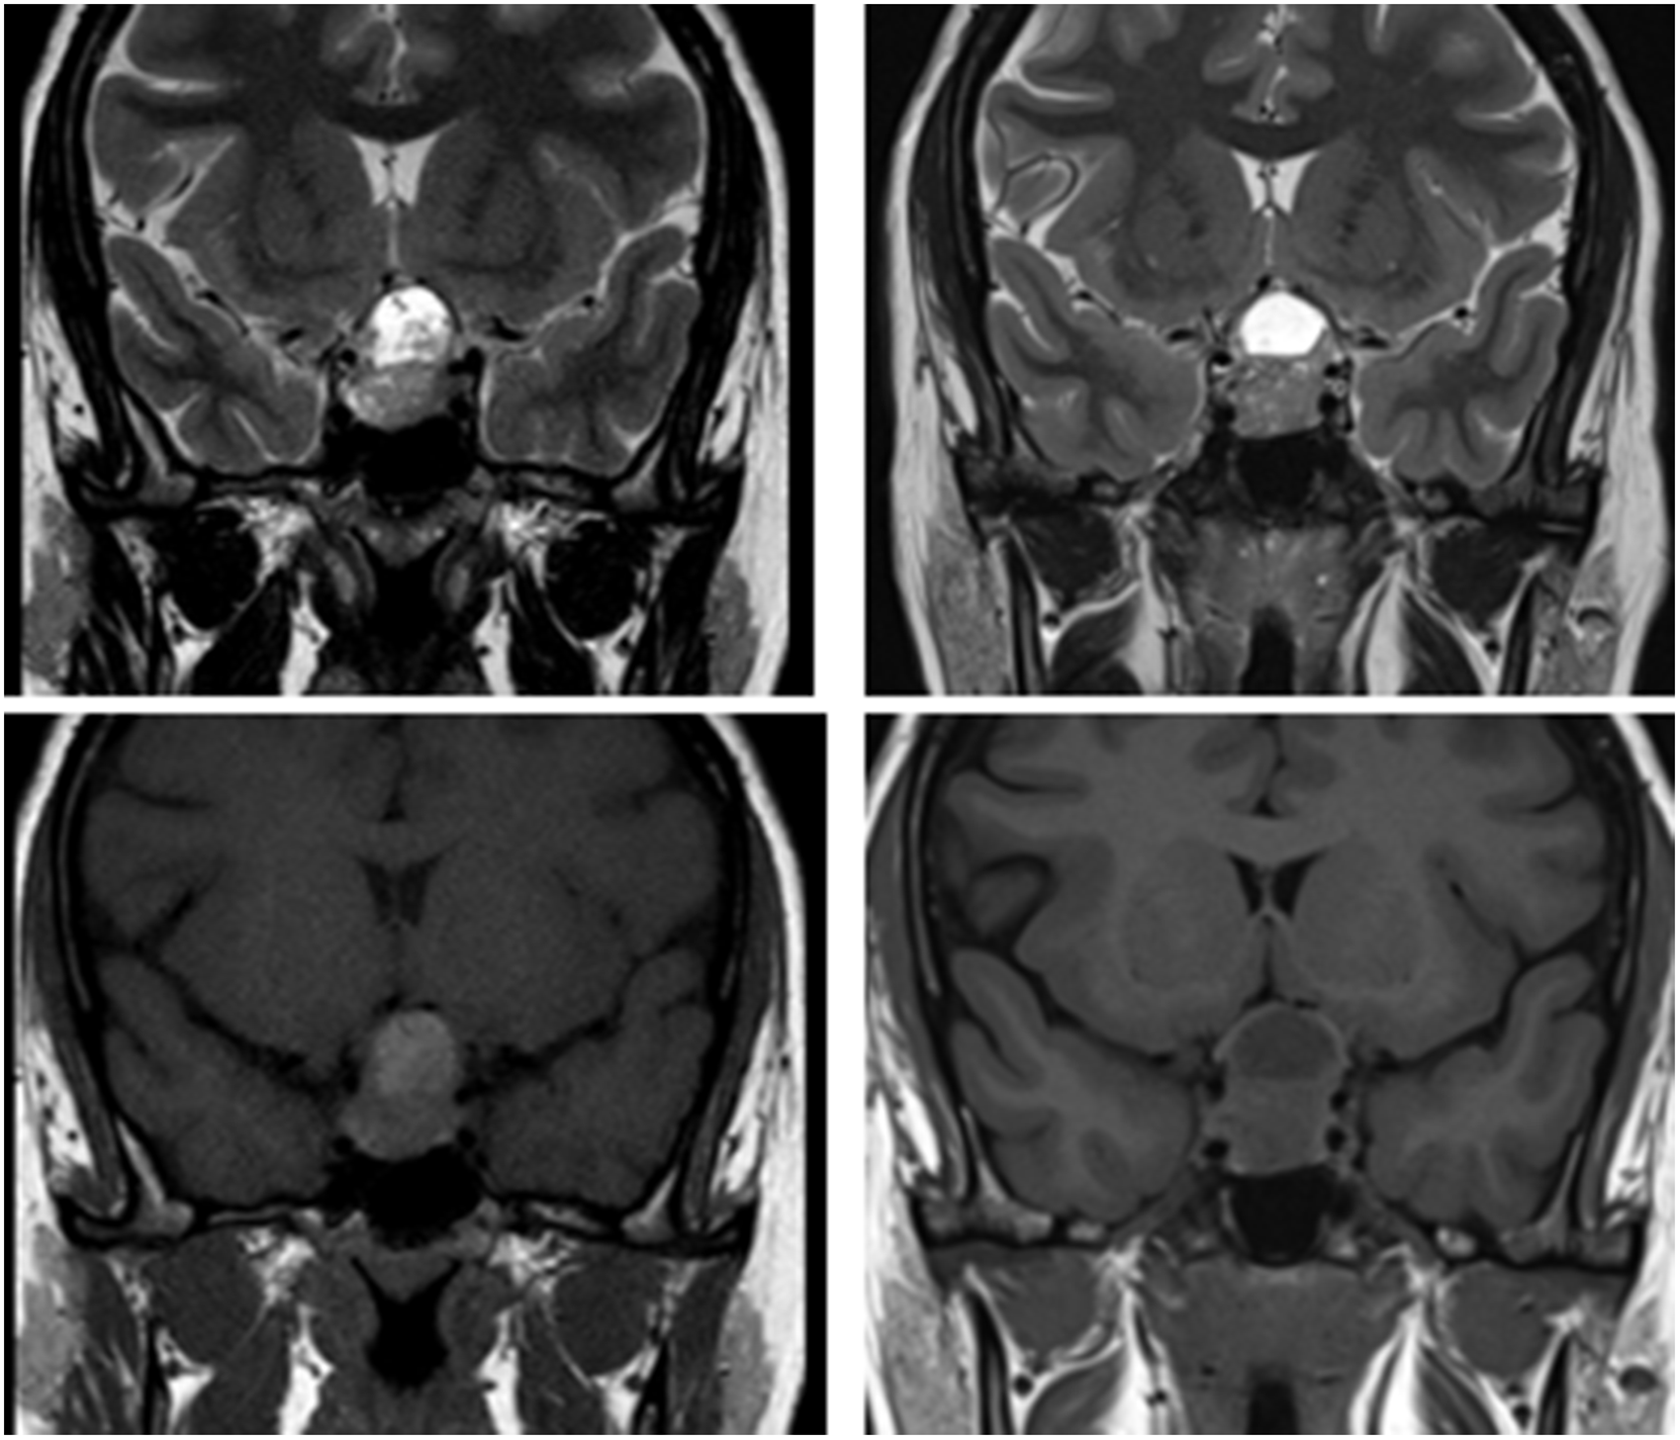

A 27-year-old woman was referred to neuro-ophthalmology for a 2-month history of left greater than right vision loss. She was 17 weeks pregnant (G5P1), but otherwise healthy and on no medications. Initial examination revealed a visual acuity of 20/20 OD and 20/30-2 OS. Humphrey 24-2 SITA-Fast visual fields (HVF) showed a left greater than right bitemporal hemianopia (Figure 1A). Optical coherence tomography (OCT) of the macular ganglion cell-inner plexiform layer (GCIPL) showed very subtle binasal thinning (Figure 1C). An MRI of the sella with contrast was performed and showed a “snowman-shaped” intrasellar and suprasellar, 24 × 20 × 17 mm mass compressing the optic chiasm (Figure 2A). The mass had cystic changes at the suprasellar component, which demonstrated intrinsic T1 hyperintensity within the cyst. The patient had normal endocrinological evaluation in the context of her pregnancy, which included normal adrenocorticotropic hormone (5.4 pmol/L), growth hormone (2.3 µg/L), prolactin (91.1 µg/L), and thyroid-stimulating hormone (1.89 µIU/mL). A neurosurgical consultation recommended surgical resection with the goal of improving and preserving her vision. The patient declined surgical intervention and decided to reconsider after delivery. Her visual field remained essentially stable throughout pregnancy. She delivered her baby via C-section after which she decided to reconsider surgery. However, she noticed a significant improvement in her visual field 5-month post-partum. She continued to notice a gradual improvement over the next several months and at the 15-month post-partum follow-up, her visual acuity was 20/20 in both eyes, HVF was normal (Figure 1B) and OCT GCIPL showed binasal atrophy (Figure 1D). A repeat MRI sella showed stable size of the intrasellar and suprasellar mass with interval decrease in T1 signal of the suprasellar cystic component (Figure 2B). There was stable mass effect on the optic chiasm and pre-chiasmatic optic nerves with the interval development of high T2-signal in the optic nerves.

Figure 2: Magnetic resonance imaging at presentation (A) demonstrating T2 (top left) and T1 sequences (bottom left) at presentation and final follow-up (B) demonstrating T2 (top right) and T1 sequences (bottom right).